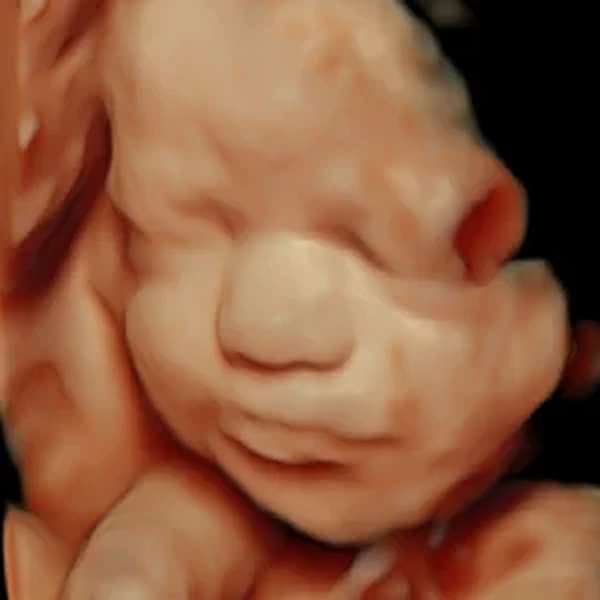

Ecografía 3D | 4D | 5D HDlive

La ecografía HDLive es una tecnología avanzada de ultrasonido en 3D y 4D que ofrece imágenes de alta resolución y realismo del feto durante el embarazo. Gracias a un sofisticado sistema de iluminación y sombreado, permite visualizar con gran detalle los rasgos faciales, movimientos y gestos del bebé en tiempo real. Es especialmente utilizada para mejorar la experiencia de los padres y facilitar la evaluación médica del desarrollo fetal. Segura e indolora, esta ecografía proporciona una visión más clara y emocionalmente impactante del bebé antes de su nacimiento.